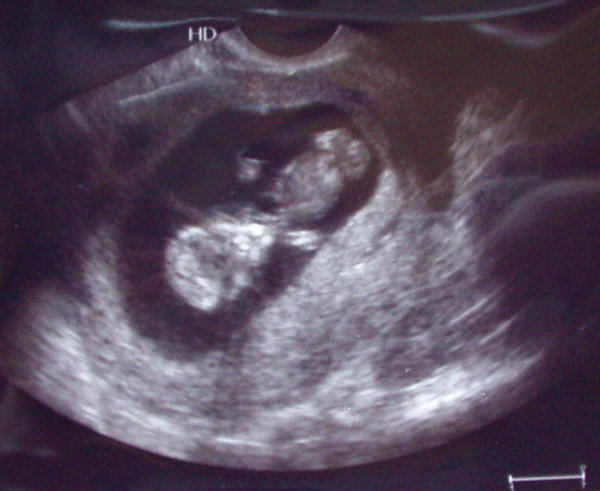

Kazincbarcikára elmentünk 11+3 hetesen uh-ra. Ez most volt reggel. Egy ismerős ott szonográfus. megcsinálta a vizsgálatot. Szerencsére rendben talált minket.

CRL: 47 mm

BDP: 17 mm

NT: 2 mm

És itt van 2 kép a kicsiről. Mindkettőn alul van a feje, és elölről lehet látni.